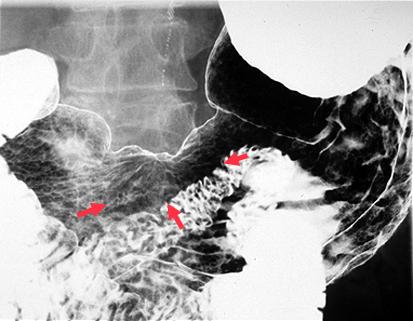

질환(병리주체)의 분류 악성 상피성종양/선암

부위(장기별) 위(부위)/위각

검사방법 X-P

종양의 육안분류 0형(표재형)/IIc형(IIc+III)

종양의 최대경(밀리미터) 25~29

종양의 심달도 m